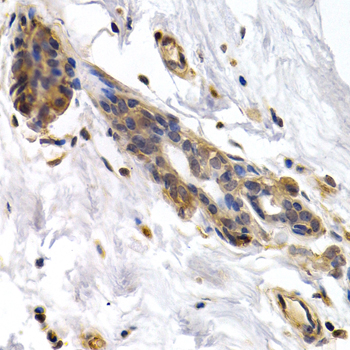

Immunohistochemistry of paraffin-embedded human normal breast using PKLR antibody at dilution of 1:200 (400x lens).